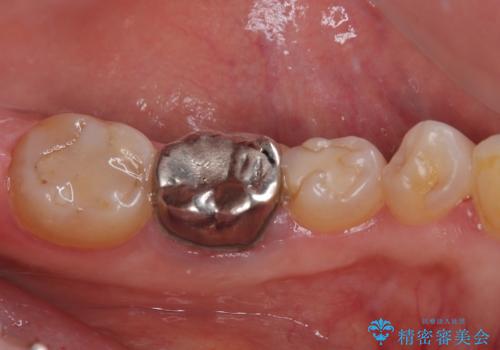

他にも銀歯や欠損となっている歯に対しての治療も希望されたため、補綴治療を行うこととしました。

インプラント治療をきっかけに、銀歯を全てセラミックに替えていきました。